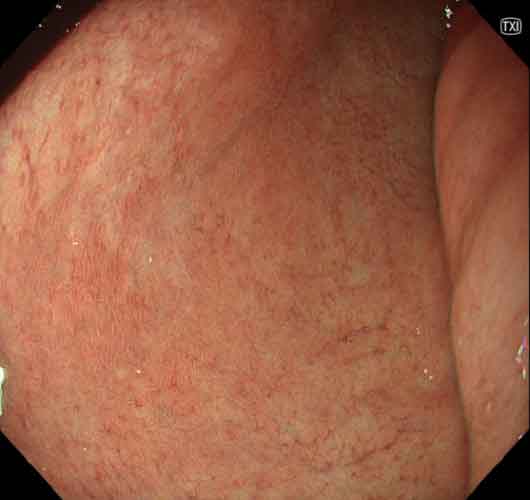

症例3(図3a~d)除菌後に診断された胃底腺型胃癌症例

TXIモード2観察では、病変は胃体部大弯に、周囲に比べて明瞭な褪色を示し、わずかに陥凹した領域として認められる(図3a)。白色光では病変の認識は可能であるが、周囲とのコントラストは弱い(図3b)。NBI観察では、同様に周囲よりわずかに白色調の領域として認識できる(図3c)。更に近接して観察すると、粗造ではあるが胃底腺粘膜の基本構造が明瞭に観察できる(図3d)。

図3 症例3 除菌後に診断された胃底腺型胃癌

• a) TXI モード2

• b) 白色光

• c) NBI

• d) NBI 近接像